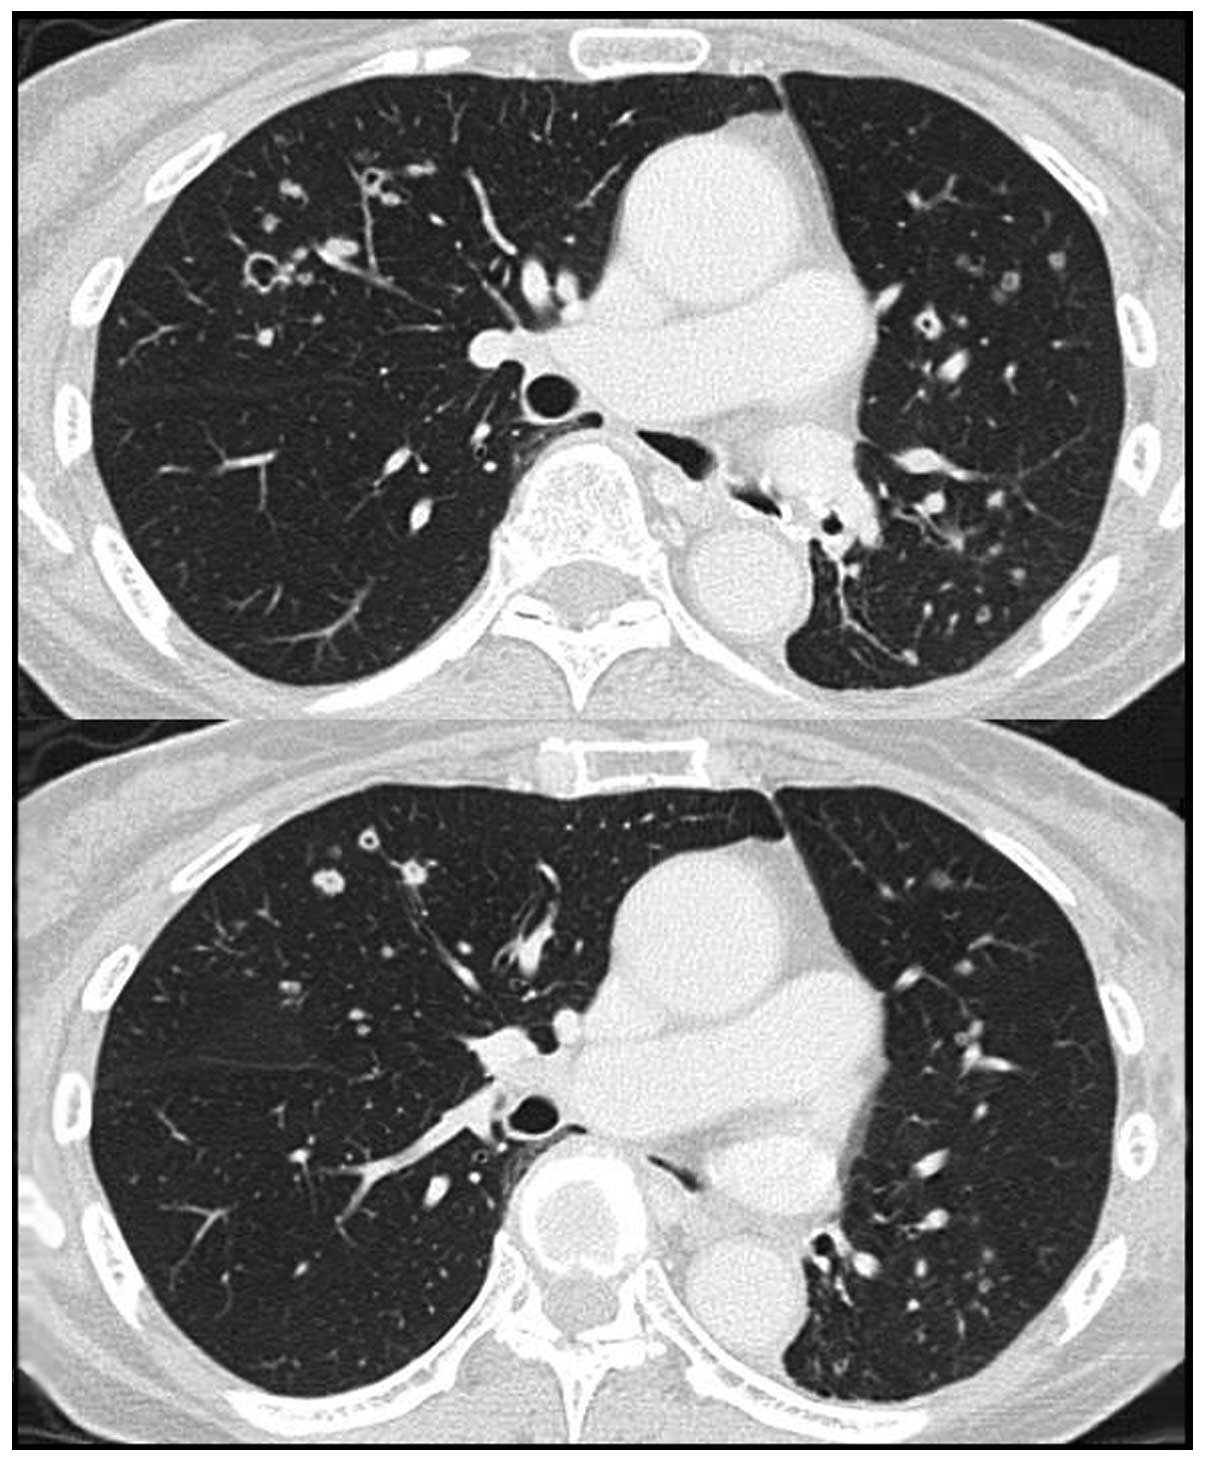

Adenosquamous cell lung cancer successfully treated with gefitinib: A case report

Although adenosquamous cell lung cancer (ASCLC) is included in the non‑small‑cell lung cancers (NSCLCs), the number of currently available studies on the response of this type of cancer to epidermal growth factor receptor‑tyrosine kinase inhibitors (EGFR‑TKIs) is limited. This is the case report of a 66‑year‑old female who was referred to the Mito Medical Center (Mito, Japan) with hemoptysis and the chest computed tomography (CT) scan revealed a large cavitary mass in the lower lobe of the left lung. The patient underwent surgical resection of the lesion and the final pathological diagnosis was ASCLC staged as pT2bN2M0. Notably, an EGFR exon 19 deletion was identified in the adenocarcinomatous as well as the squamous cell carcinomatous components of the tumor. Despite adjuvant chemotherapy, the patient developed small cavitary metastases in the lungs bilaterally. Therefore, treatment with gefitinib was initiated. The chest CT scan revealed substantial regression of the metastatic cavitary tumors in both lungs, with thinning of the walls. The patient remains alive and recurrence‑free 19 months following the initiation of gefitinib therapy. This case demonstrated an optimal clinical response to gefitinib treatment for EGFR mutation‑positive ASCLC, suggesting that gefitinib is a therapeutic option for such a subset of patients with ASCLC.

Figure 2

Figure 3